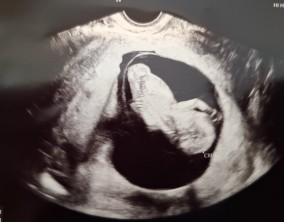

믿음 끝에 찾아온 첫 기적

의료진분들의 따뜻한 말 한마디와 친절한 행동 하나하나가 힘든 난임 치료 과정에서 큰 도움이 되었습니다. 그 진심 어린 마음이 앞으로도 많은 난임 부부들에게 변함없이 전해지…